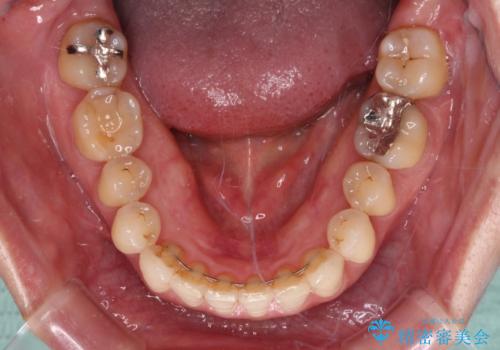

- 下顎の八重歯と、上下のクロスバイトを気にして来院された患者様です。

インビザラインを用い、下顎全体の後方移動、IPR(歯と歯の間を削る)と歯列全体を拡大させることで、歯並びを整えていくこととしました。

奥に位置していた上の前歯が下の前歯を乗り越える際、奥歯でものを咬むことができず、辛い時期が続きました。